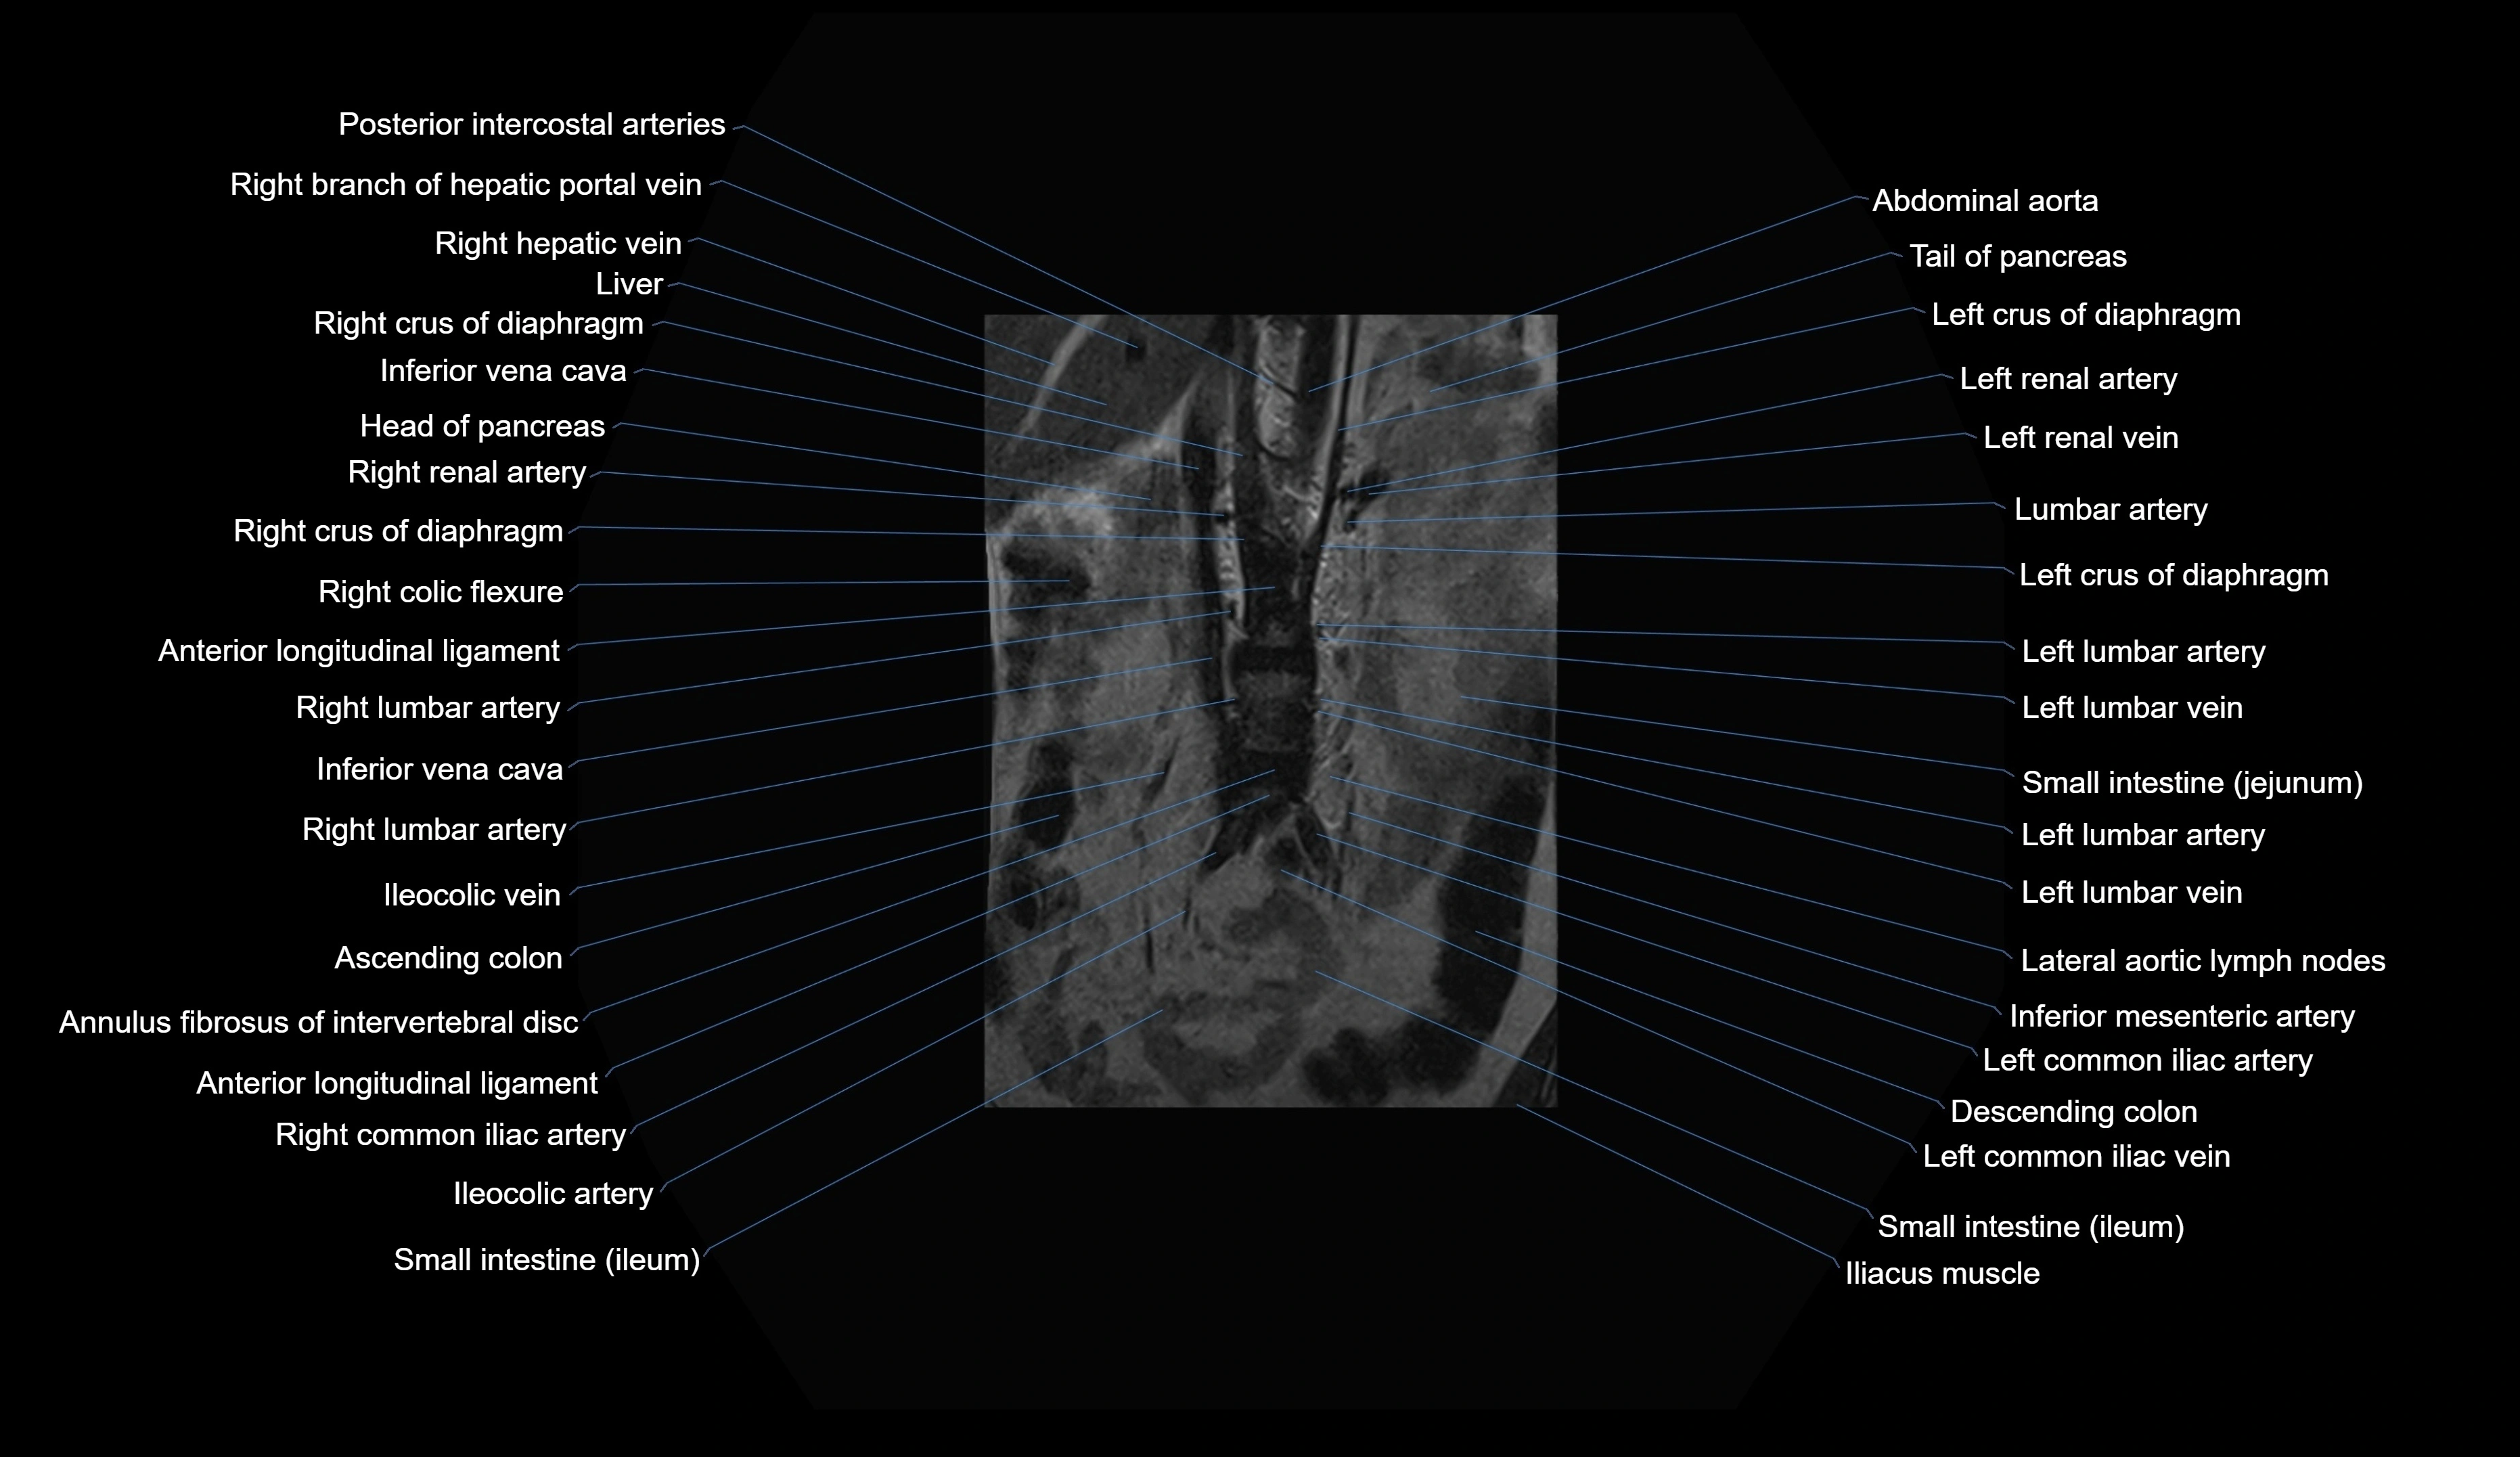

MRI images